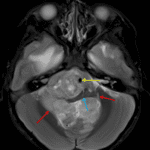

MRI

- Large, heterogeneously enhancing mass arising at the floor of the fourth ventricle and extending through the right greater than left foramina of Luschka and foramen of Magendie into the prepontine and premedullary cisterns and upper cervical spinal canal

- Extensive corresponding mass effect on the cerebellum, pons, medulla, and upper cervical spinal cord

- T2 signal intensity is similar to that of gray matter

- A few foci of internal susceptibility artifact likely represent calcification in correlation with the CT

- Encasement of the basilar and intradural vertebral arteries